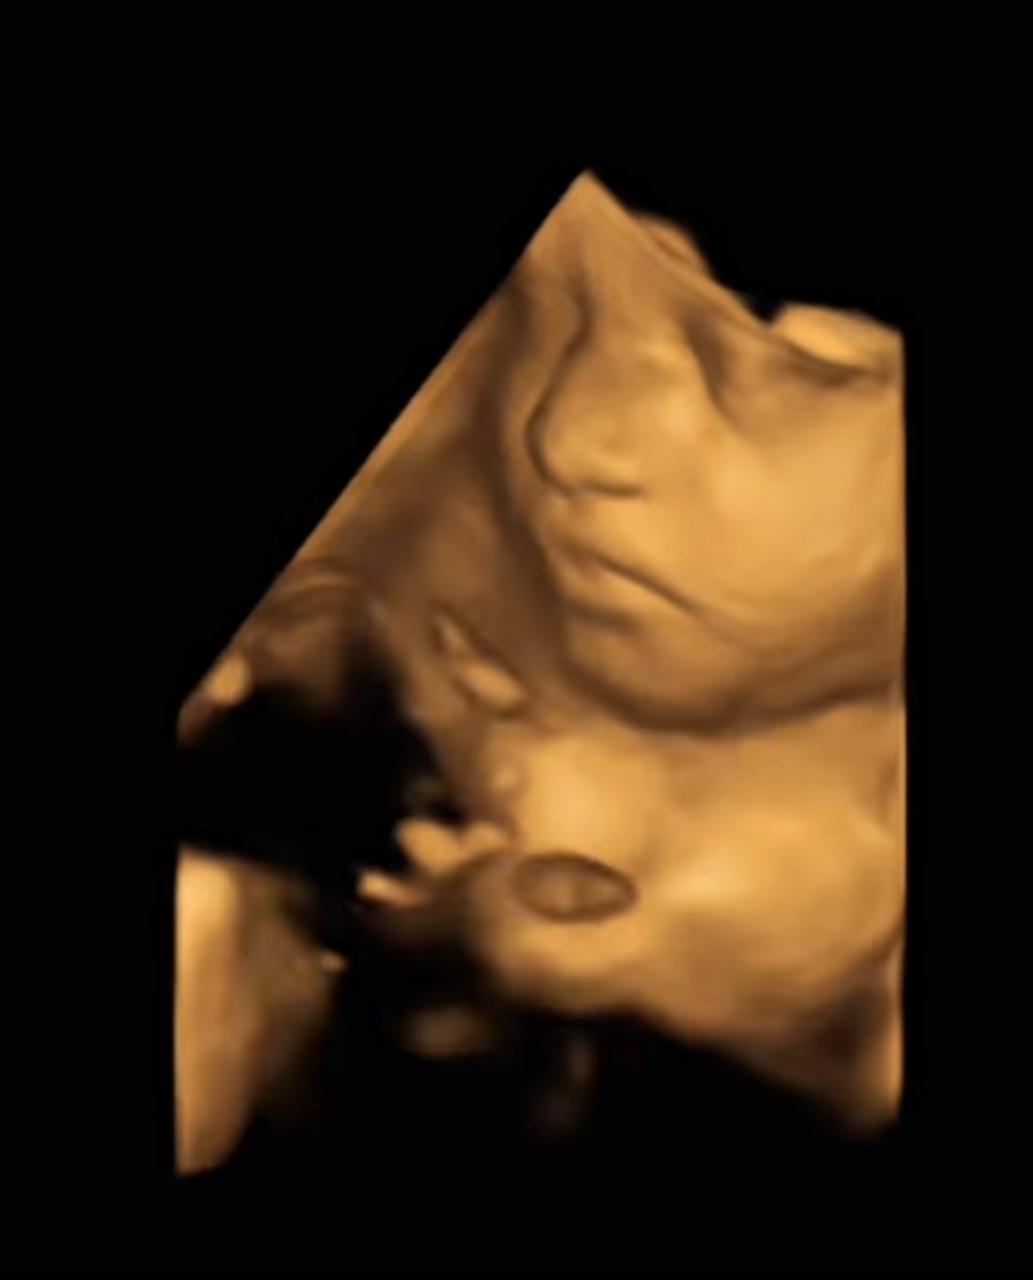

A glimpse of little smiles and joy

Explore our journey of advanced treatments, cutting-edge technology, and compassionate care. Our gallery showcases real procedures, patient stories, and the environment where healing begins.

3D Imaging

3D Photo